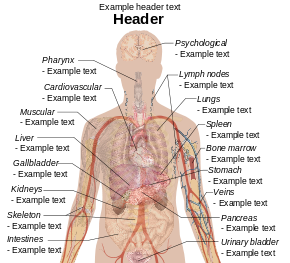

English: Main symptoms of different variants and stages of tuberculosis (See Wikipedia:Tuberculosis), with many symptoms overlapping with other variants, while others are more (but not entirely) specific for certain variants. Multiple variants may be present simultaneously.

Pulmonary tuberculosis symptoms

Extrapulmonary tuberculosis symptoms